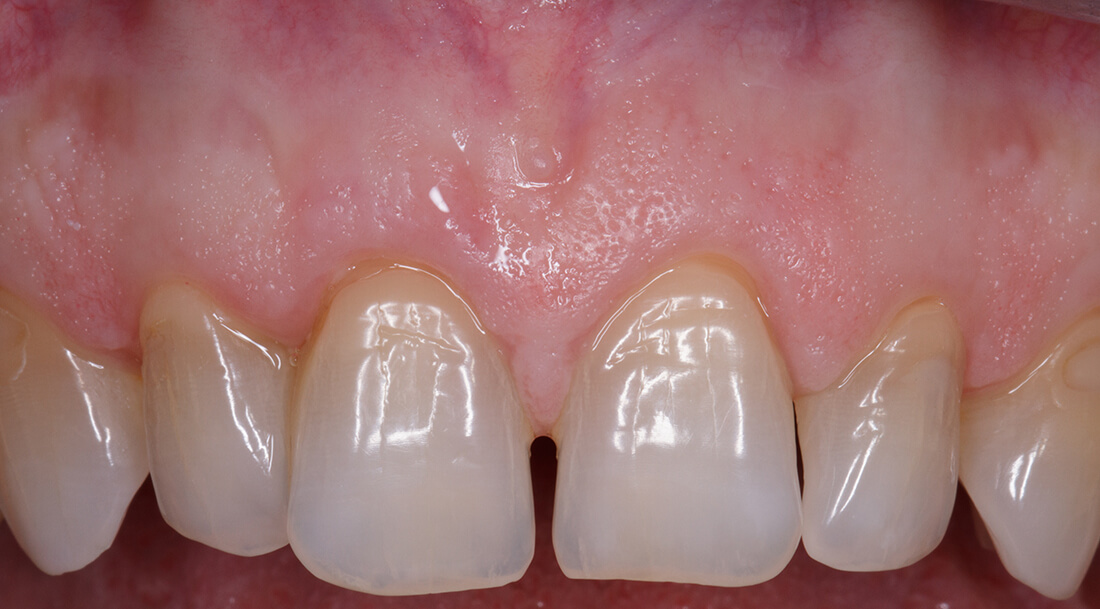

Canino superiore con recessione: prima e dopo Intervento di Chirurgia Mucogengivale con sostituti dermici

Quando le recessioni sono iniziali è sufficiente modificare le tecniche di spazzolamento e tenere le lesioni sotto controllo.

Quando iniziano a diventare un problema estetico, soprattutto nei denti anteriori , quando il paziente accusa molta sensibilità o i denti tendono a cariarsi sulla porzione di radice scoperta la Chirurgia Mucogengivale è in grado di riportare le gengive a dei livelli corretti.

La tecnica chirurgica prevede spesso il prelievo di una porzione di mucosa prelevata dal palato che andrà inserita nella zona della recessione gengivali. Questo normalmente causa un notevole fastidio al paziente nella zona di prelievo dal palato.

Da più di 15 anni la ricerca sui biomateriali ha messo a disposizione degli ottimi sostituti connettivali che evitano il prelievo di connettivo dal palato.

Per il trattamento chirurgico di circa 1.500 recessioni gengivali il dr. Patarino Domenico ha sempre utilizzato i biomateriali sostituti dermici, evitando il prelievo dal palato, con ottimi risultati clinici, evitando le complicanze possibili di questo intervento e diminuendo di molto il dolore e il gonfiore post-operatorio dei suoi pazienti.